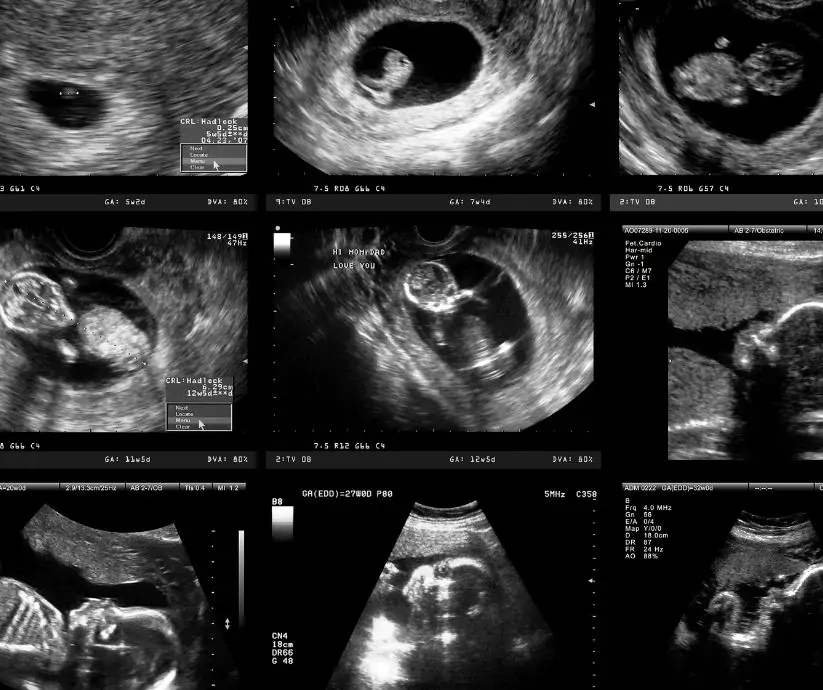

W trakcie ciąży wykonuje się trzy obowiązkowe badania ultrasonograficzne rozwijającego się płodu. USG pierwszego trymestru powinno zostać wykonane właśnie w 3 miesiącu ciąży, czyli między 11. a 14 tygodniem (po ukończeniu 11, a przed rozpoczęciem 14 tygodnia ciąży). Potocznie to badanie nazywa się USG genetycznym – pozwala bowiem na wykrycie cech świadczących o ewentualnych chorobach genetycznych płodu.

Między 11. a 14 tygodniem ciąży płód jest już na tyle rozwinięty, że doświadczony lekarz posiadający uprawnienia i aktualne certyfikaty do wykonywania badań prenatalnych może szczegółowo ocenić jego rozwój. USG w pierwszym trymestrze ciąży służy więc ocenie:

• liczby płodów (ciąża pojedyncza / ciąża mnoga),

• pomiarów biometrycznych płodu,

• anatomii dziecka (czaszki i mózgu, kręgosłupa, kończyn, klatki piersiowej i serca, jamy brzusznej),

• czynności serca płodu (FHR – fetal heart rate),

• przezierność karku płodu (NT – nuchal translucency),

• ocenie kosmówki.

W tym badaniu oceniane są tzw. markery chorób genetycznych, czyli ściśle określone cechy ultrasonograficzne umożliwiające wykrycie najczęściej spotykanych u dzieci wad genetycznych, takich jak zespół Downa, zespół Edwardsa czy zespół Patau.

USG w pierwszym trymestrze ciąży – jak przebiega?

Badanie jest wykonywane w pozycji leżącej na plecach. Pacjentka wchodzi do gabinetu, kładzie się na leżance i zostaje poproszona o odsłonięcie brzucha. Następnie lekarz przykłada do skóry posmarowaną żelem głowicę emitującą ultradźwięki (żel ułatwia ich wnikanie w głąb tkanek i sprawia, że głowica lekko porusza się po ciele). Na monitorze od razu widoczne są obrazy – lekarz, obserwując je, ocenia rozwój płodu. Badanie trwa z reguły od 15 do 20 minut.

W trzecim miesiącu płód ma wielkość od 2,6 do 5,5 centymetra, a w brzuszku przyszłej mamy jest jeszcze dużo miejsca. Choć ruchy dziecka w 10. tygodniu ciąży są już zauważalne w badaniu USG, a płód ćwiczy rączki, nóżki i palce, to przyszła mama zazwyczaj jeszcze nie może ich wyczuć.

To również czas na USG prenatalne – 12. tydzień ciąży jest idealnym momentem na jego wykonanie, dlatego jeśli Twój lekarz posiada odpowiednie uprawnienia, prawdopodobnie przeprowadzi je podczas wizyty.

W trzecim miesiącu ciąży narządy płciowe są w pełni ukształtowane, ale zazwyczaj nie są jeszcze dobrze widoczne podczas pierwszego badania ultrasonograficznego. Zdarza się jednak, że dziecko jest dobrze ułożone i można określić płeć. Często jednak zdarza się, że na kolejnym badaniu może się to diametralnie zmienić. Bardziej precyzyjne może okazać się badanie połówkowe około 20. tygodnia ciąży.